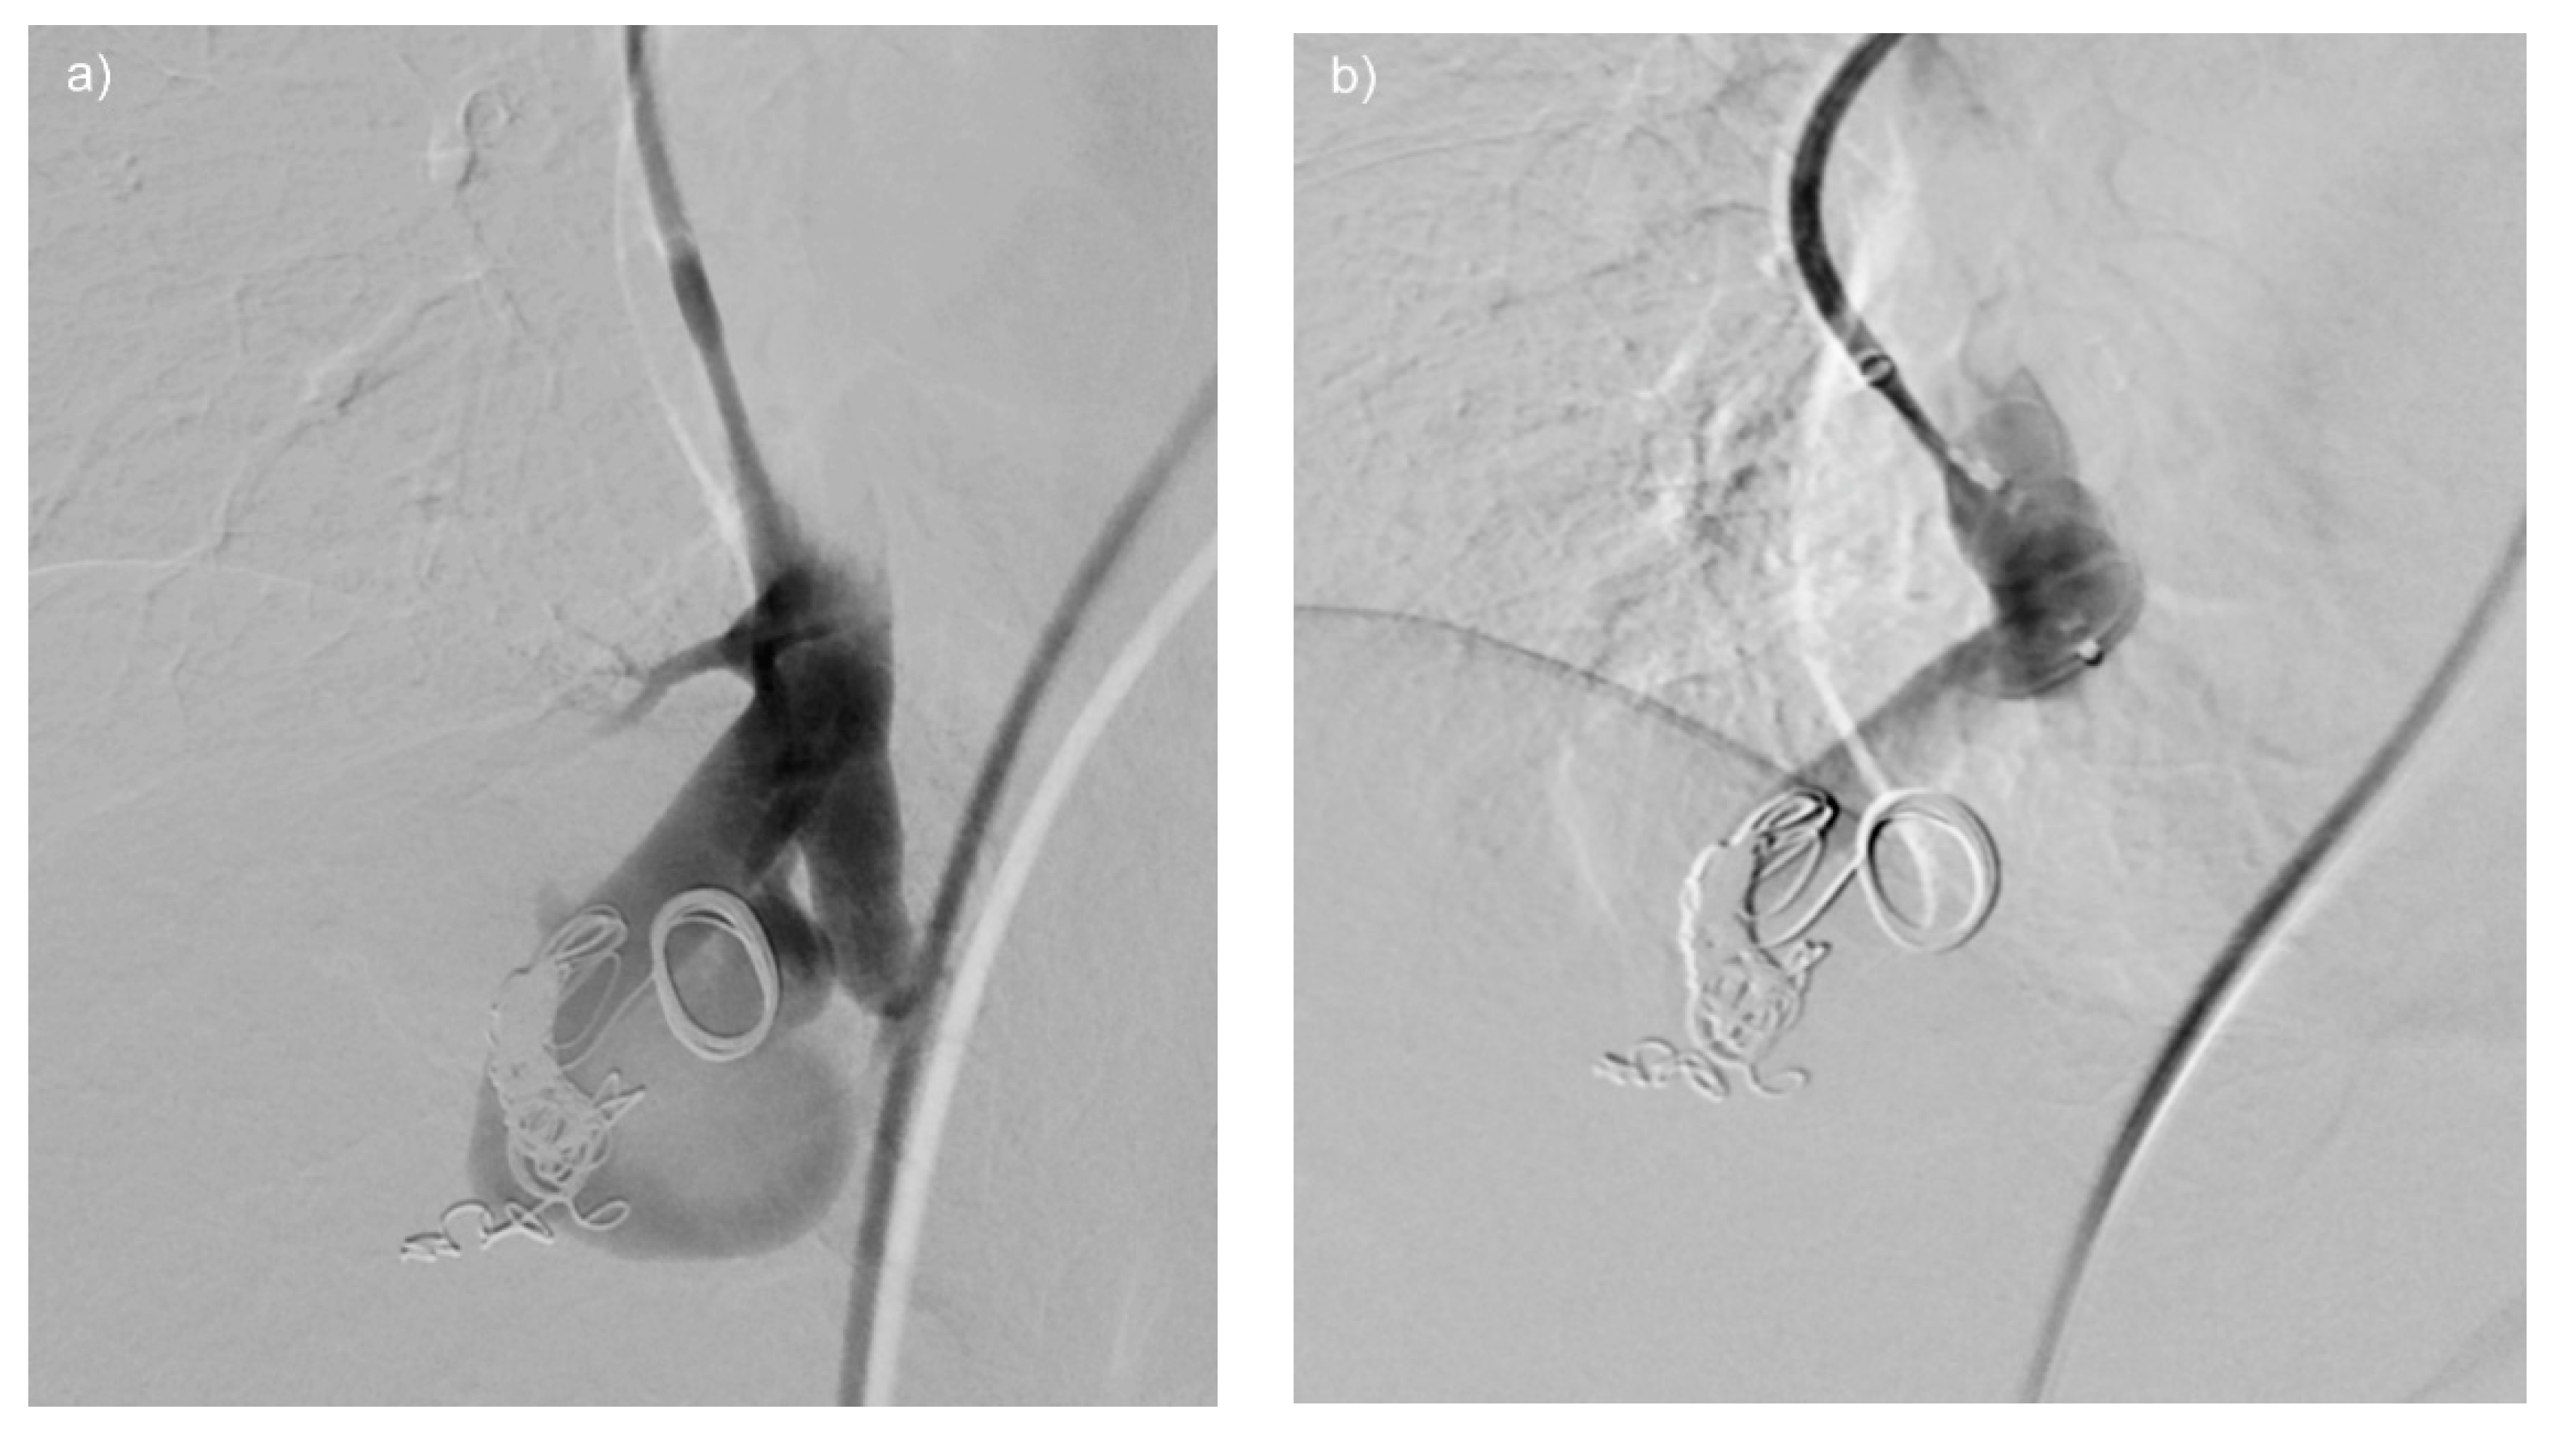

Figure 2. (ac) CT of a patient, demonstrating a giant complex PAVM of the right lung (a). The PAVM is depicted after selective catheterization of the feeding artery on DSA after manual contrast medium injection (b). DSA of the PAVM directly after positioning of an amplatzer vascular plug II (arrow) with already reduced flow in the PAVM (c).